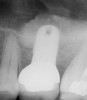

Once it is determined that the twist drill (2.1-mm diameter) is within 1 mm of the sinus floor, the second drill (2.8-mm diameter) and third drill (3.5-mm diameter), if desired, are used to penetrate to within 1 mm of the sinus floor (Figure 3). The amount of osteotomy widening is dependent upon tactilely perceived bone quality.

Figure 3  The osteotomy was completed with the 2.1-, 2.8-, and 3.5-mm twist drills without penetrating into the sinus.

Figure 3